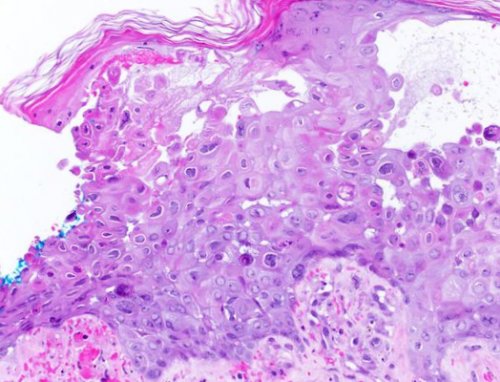

Патоморфологические изменения кожи

— клетки шиповатого слоя

• происходит баллонирующая дегенерация | |

• появляются гигантские клетки, которые содержат несколько

клетки — симпласты — с внутриядерными включениями • везикулёзная — покраснение с образованием поражения плода/ребёнка.и зависят от реакций.мазков-отпечатков из высыпаний: обнаруживаются гигантские многоядерные • эритематозная — покраснения;и не вызывает

с эозинофильными включениями.